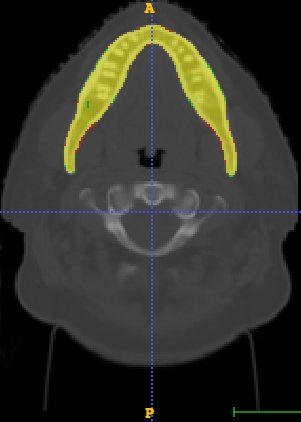

In Chapter 6, we propose an end-to-end, atlas-free 3D convolutional deep learning framework for fast and fully automated whole-volume HaN anatomy segmentation [115]. Our deep learning model, called AnatomyNet, segments OARs from head and neck CT images in an end-to-end fashion, receiving whole-volume HaN CT images as input and generating masks of all OARs of interest in one shot. AnatomyNet is built upon the popular 3D U-net architecture, but extends it in three important ways: 1) a new encoding scheme to allow auto-segmentation on whole-volume CT images instead of local patches or subsets of slices, 2) incorporating 3D squeeze-and-excitation residual blocks in encoding layers for better feature representation, and 3) a new loss function combining Dice scores and focal loss to facilitate the training of the neural model. These features are designed to address two main challenges in deep-learning-based HaN segmentation: a) segmenting small anatomies (i.e., optic chiasm and optic nerves) occupying only a few slices, and b) training with inconsistent data annotations with missing ground truth for some anatomical structures. We collect 261 HaN CT images to train AnatomyNet, and use MICCAI Head and Neck Auto Segmentation Challenge 2015 as a benchmark dataset to evaluate the performance of AnatomyNet. The objective is to segment nine anatomies: brain stem, chiasm, mandible, optic nerve left, optic nerve right, parotid gland left, parotid gland right, submandibular gland left, and submandibular gland right. Compared to previous state-of-the-art results from the MICCAI 2015 competition, AnatomyNet increases Dice similarity coefficient by 3.3% on average. AnatomyNet takes about 0.12 seconds to fully segment a head and neck CT image of dimension , significantly faster than previous methods. In addition, the model is able to process whole-volume CT images and delineate all OARs in one pass, requiring little pre- or post-processing. We demonstrate that our proposed model can improve segmentation accuracy and simplify the auto-segmentation pipeline. These contributions are released as an open-source software package called AnatomyNet, which is publicly available555https://github.com/wentaozhu/AnatomyNet-for-anatomical-segmentation. Portions of this chapter were published as part of [115].